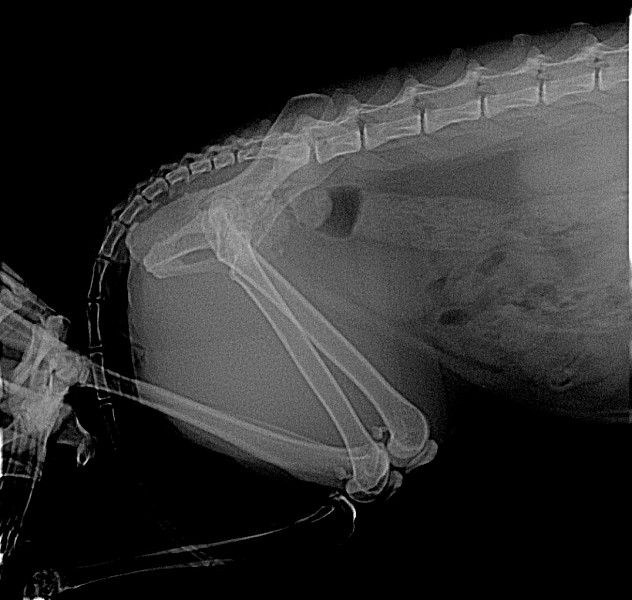

Рентгенологическая диагностика саркомы у кошек

Раздел: Визуальный дайджест